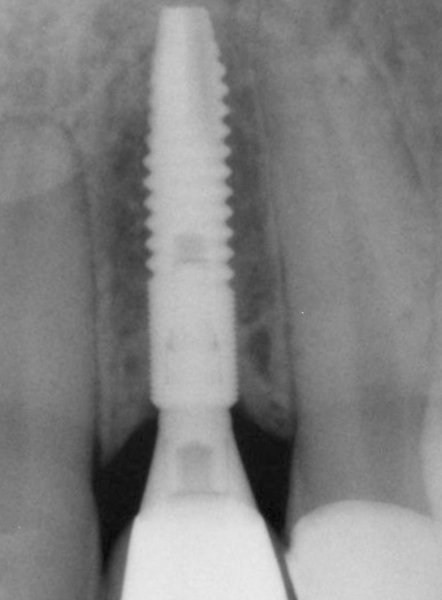

Web Implant systems Astra Tech Implant system. Shop now Created with Sketch. The placements of their prosthetic components are very simple to master.

Web Be the first to write a review. Reviews manufacturer warranties advantages and disadvantages in the life of a modern person who wants to become successful one of the. With over 30 years in the market and documented in over 1000 peer-reviewed scientific studies a survival rate of over 98.

Web One of the most well-documented implant systems in the market today documented in over 1000 publications in peer-reviewed journals the Astra Tech. With the ASTRA TECH Implant System esthetics are integrated into the implant system. Web Clinical procedures only Maxillary anterior single tooth case Chapter 4 410Case presentationSurgical and restorative procedures for a single case insta.